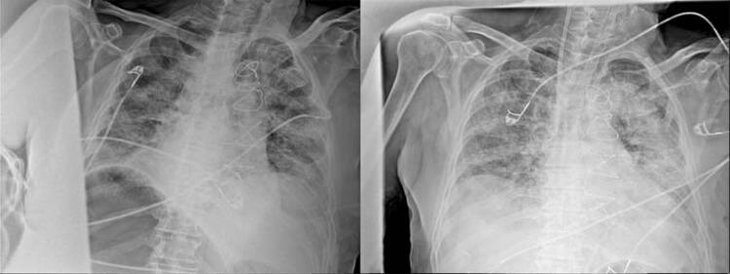

Ankara Şehir Hastanesinde koronavirüs tedavisi gören hastalara ait akciğer görüntülerine ulaştı. Görüntülerde, hastalığın ne kadar hızlı ilerlediği ve akciğerleri nasıl tuttuğu ortaya çıktı.

Prof. Dr. Karalezli, koronavirüs tedavisi gören hastalara ait akciğer görüntülerinden hastalığın yol açtığı tahribatı ve hastalar üzerindeki etkileri anlattı.

Tedavisine rağmen nefes darlığı şikayetleri devam eden bir hastaya uygulanan akciğer görüntülemesinde hastanın her iki akciğerinin büyük bir bölümünü enfeksiyon kapladığını tespit ettiklerini ifade eden Karalezli, "Bu hastalığın sonunun ne olduğunu bilmiyoruz. Akciğer tutulumları, bu şekilde olduğu zaman hastaları oksijen tedavisi ile gönderiyoruz."